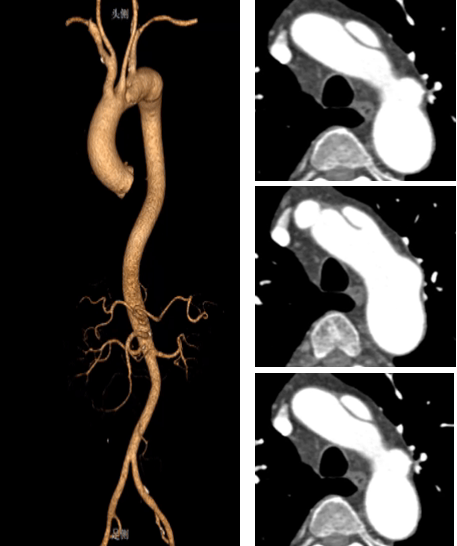

★ 病例2:模块内嵌分支胸主动脉覆膜支架系统

术前

术后